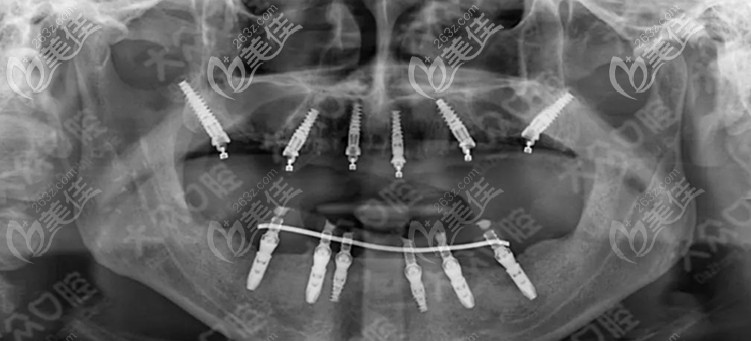

曾带领着种植团队把复杂软硬组织增量、All-On-Four半/全口种植牙、Comfour系统的即刻种植以及穿颧穿翼V-Ⅱ-V等种植技术应用于临床。

何为上颌翼板区种植技术?

是通过上颌结节到翼板区的种植统称为上颌翼板区种植,相比传统的种植牙技术,翼板种植技术的优势则在于:

解决了牙槽骨流失“无法种牙”的大难题,翼板种植不需要植骨,牙槽骨极度萎缩的顾客也可以通过翼板受力实现上颌即刻负重,还能保留上颌窦的完整性。

目前武汉爱尚大众口腔的周先略就能开展穿翼板VIIV即刻种植手术,且已有多例成功的案例供顾客参考。